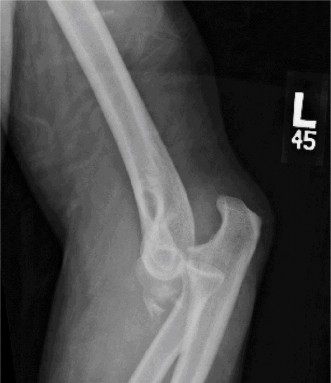

Examination reveals deformity about the elbow with no open lesions or skin tenting. He has a palpable radial and ulnar pulse and is neurologically intact. His images are shown (Figs. 2–85 to 2–88).

Figure 2–85

Figure 2–86

Figure 2–87

Figure 2–88

What is the diagnosis and direction of displacement?

- Monteggia fracture dislocation, posterolateral displacement of the forearm about the humerus

- Simple elbow dislocation, posterolateral displacement of the forearm about the humerus

- Transolecranon complex elbow dislocation

- Simple elbow dislocation, posteromedial displacement of the forearm about the humerus

Discussion

The correct answer is (B). This is the most common type of elbow dislocation, and often does not cause any osseous injury. Posterolateral and posteromedial dislocation account for approximately 90% of dislocations. Adequate pre- and postreduction films are necessary to evaluate for fracture, which would change the classification to a complex injury.